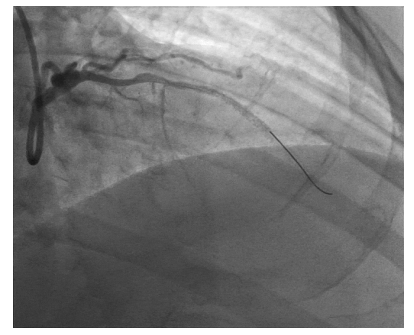

后:支架植入术后